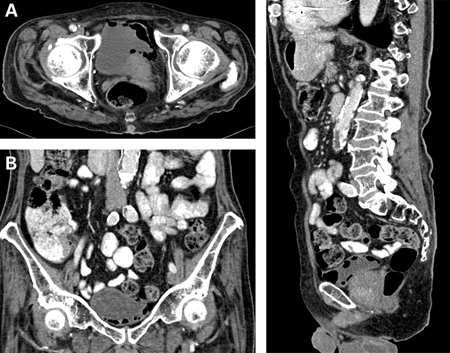

Emphysematous cystitis: (A) horizontal CT slice showing increased emphysema, (B) coronal CT slice showing increased emphysema, (C) sagittal CT slice showing increased emphysema

Middela S, Green E, Montague R. Emphysematous cystitis: radiological diagnosis of complicated urinary tract infection. BMJ Case Rep. 2009; doi:10.1136/bcr.05.2009.1832. Used with permission